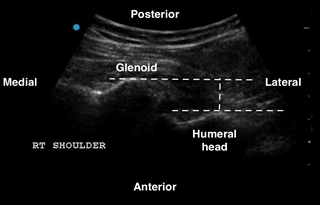

An anterior shoulder dislocation will show the humeral head displaced to the far field region of the screen, while the posterior dislocation will show the humeral head displaced to the near field region (Figures 3 and 4). A shoulder subluxation will show the humeral head partially sliding (or “dislocating”) in and out of the GHJ with shoulder movement (Figure 5). While less accurate, POCUS can also help identify fractures, such as the Hill-Sachs, the Bankart, or a humeral head fracture (Figure 6).

Secko MA, et al. has estimated a 100% sensitivity and specificity in diagnosing a shoulder dislocation by using the posterior approach technique. They also established that an anterior dislocation has a glenohumeral distance cutoff value of at least 0.5 cm.6

Figure 2: Right shoulder anterior dislocation